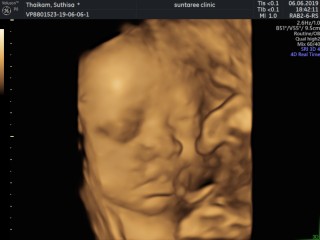

ซาวตอน21w ค่ะ